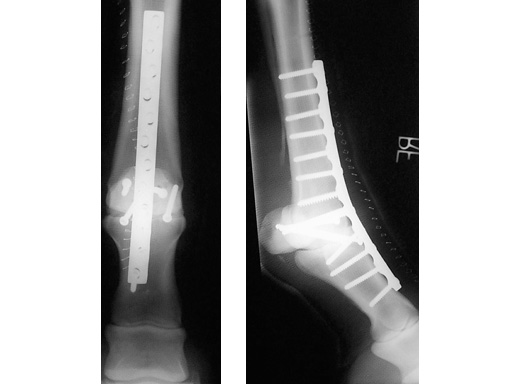

5.5 mm Broad LC-DCP

The use of the 5.5 mm Broad LC-DCP is indicated in treating equine long bone fractures. The plate features the limited contactdynamic compression plate designand is made of stainless steel. It is 5.7 mm thick, 16 mm wide, and available in lengths from 178 mm (10 holes) up to 322 mm (18 holes). The existing 5.5 mm Cortex Screws can be used with this plate.

Case 1: 3-year-old thouroughbred.

The arthrodesis was necessary, because the animal suffered a breakdown injury during a race.